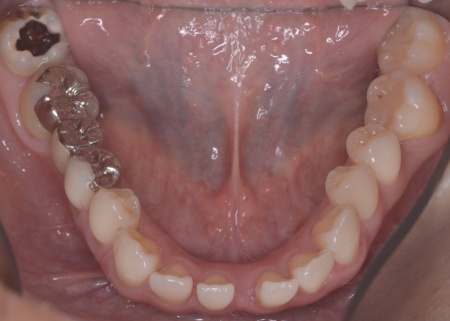

40代女性 矯正治療で噛み合わせを整えたあとセラミックの被せ物・詰め物で修復した症例

拝見したところ、左下と右上の歯はともに大きな虫歯があり、歯だけでなく被せ物を支える土台の部分にも影響が及んでいました。

さらに、ほかの歯に入っている詰め物や被せ物の周囲にも、過去に治療した部分に再び虫歯ができる二次カリエスが複数見つかりました。

また、噛み合わせを確認したところ、奥歯で噛み合わせた際に上下の前歯が当たらず隙間ができる開咬(かいこう)が認められました。

開咬は前歯で食べ物を噛み切りにくくなるだけでなく、噛む力のバランスが崩れて奥歯に負担が集中しやすくなります。

実際に患者様の場合も、特定の歯に長期間強い力がかかり続けたことで歯や修復物の破損、さらには口腔内全体のトラブルにつながった可能性が高いと考えられました。